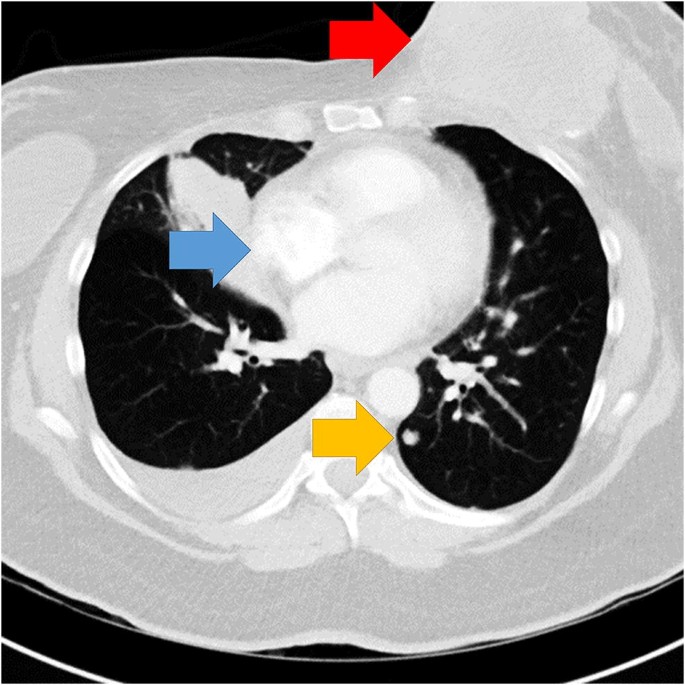

Observers evaluated seven axial chest CT scans (i practice and six experimental) in a typical lung window level. Iii experimental cases were normal and three independent lung nodules. The terminal case independent a large breast mass and lymphadenopathy in addition to lung-cancer (run across Fig. 1). The mass was nine.1vcm in maximum diameter and was visible on 17/66 slices. At its maximum diameter, the breast mass was approximately xxx times the size of the smallest lung nodules. This case, obtained from clinical practice of author Due west.A., was called because the abnormalities were deemed clearly visible using lung window level settings. Our goal was to use a case with abnormalities that would be easily detected and unambiguous if the radiologist were explicitly looking for them. The remaining images and nodule locations were obtained from the Lung Prototype Database Consortium (LIDC; Armato et al., 2011). The practice case had viii lung nodules, and the aberrant experimental cases contained fourteen.33 nodules on boilerplate (nine, eleven, & 23 per instance). The last, critical case had eleven nodules. For the cases obtained from the LIDC, ground truth was established by four thoracic radiologists that marked nodule locations prior to reviewing the anonymized marks of the other 3 radiologists and rendering a last decision (Armato et al., 2011). For the concluding case, writer W.A. marked the nodule locations.

Fig. 1

figure 1

Unmarried-slice of the chest CT showing the abnormalities. Arrows indicate the location of the chest mass (red arrow), lymphadenopathy (bluish arrow), and a lung nodule (yellow arrow). Arrows not present in experimental display